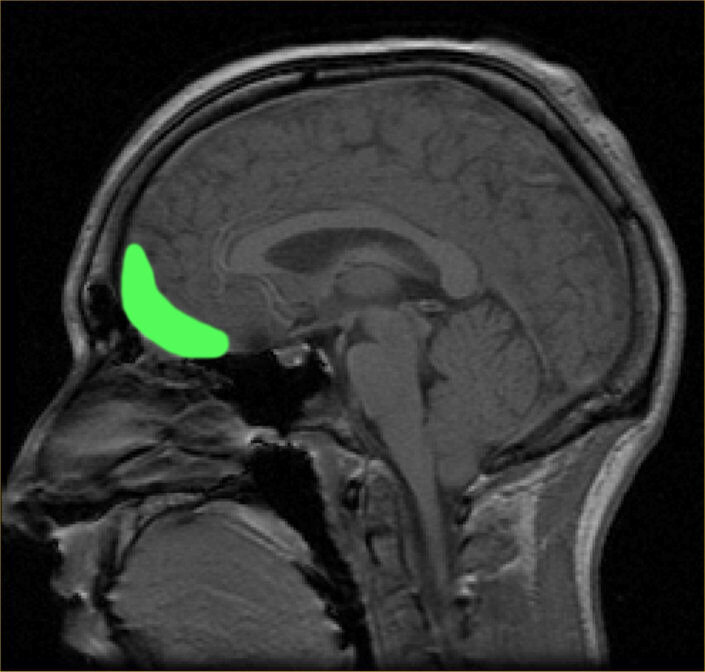

امآرآی انتشاری که ریزساختار و سازماندهی سلولی را بررسی میکند به این پژوهشگران امکان داد که به مرز میان ماده سفید و خاکستری در قشر مغز، بیرونیترین سطح مغز، نگاه کنند.

لیپتون میگوید: «ما به این منطقه مرزی نگاه کردیم زیرا ماده سفید و خاکستری چگالیهای متفاوتی دارند و در پاسخ به ضربه سر با سرعتهای متفاوتی حرکت میکنند. این امر باعث ایجاد نیروهای برشی بین دو نوع بافت میشود و منطقه مرزی میان دو لایه را در معرض آسیب قرار میدهد.»

کسانی که بیشتر سر زدن در فوتبال را داشتند – بیش از ۱۰۰۰ ضربه در سال- انتقالهای به طور قابل توجهی مبهمتری بین ماده خاکستری و سفید در ناحیه اوربیتوفرونتال مغز (پشت پیشانی) داشتند، اما در سایر مناطق دورتر مغز اینطور نبود. بازیکنانی که بیشتر اوقات به توپ ضربه سر میزدند، همچنین در آزمونهای یادگیری و حافظه در مقایسه با بازیکنانی که ضربه سر کمی زده بودند یا اصلاً نزده بودند، چند نمره پایینتر آوردند.